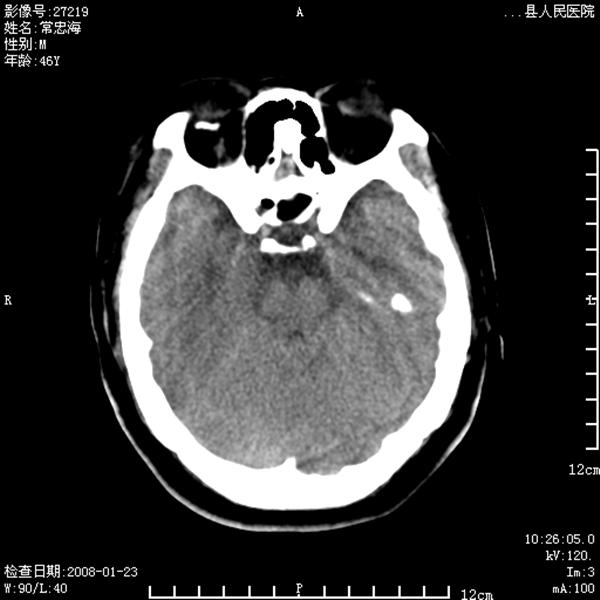

以下是引用江边学者在2008-4-19 22:26:00的发言:[br]1.胼胝体发育不良。[br]2.右侧眼球痨。[br]3.右侧颜面部软组织挫伤。